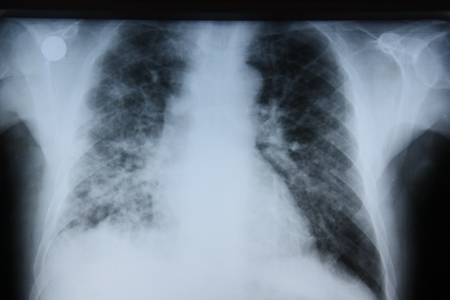

The disease typically affects patients with asthma or cystic fibrosis, but it is also associated with diminished immunity. Serology for Aspergillus may help to support the diagnosis. Skin-prick sensitivity for the organism is also a useful diagnostic adjunct.[Figure caption and citation for the preceding image starts]: Chest x-ray of a patient with eosinophilic pneumoniaFrom the collection of Athanasia Pataka, MD [Citation ends].